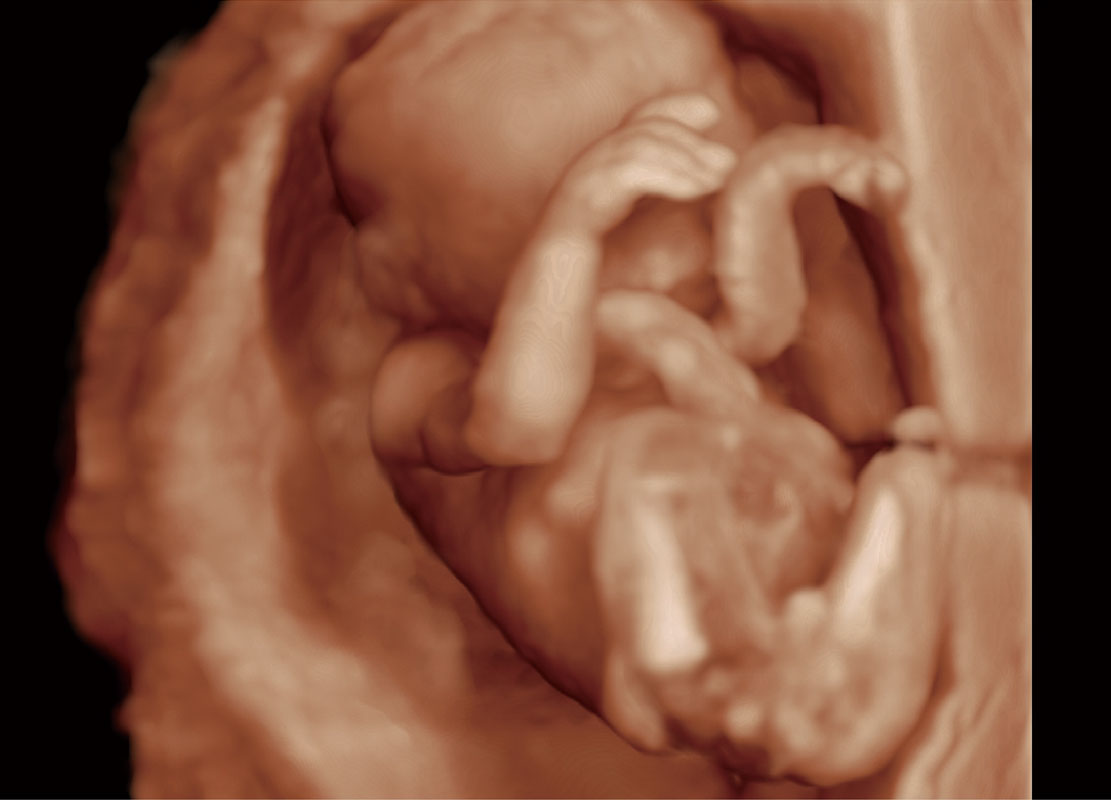

早孕筛查

P60在胎儿早孕期超声筛查中为您带来优异的图像质量。

• 高分辨率容积成像-早孕胎儿

• 胎儿体循环